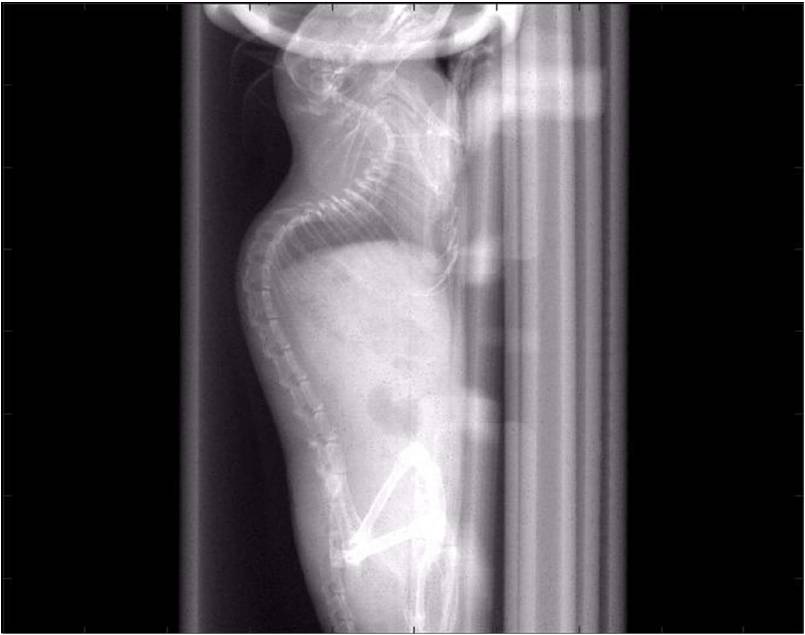

ChiPet 100是一款針對離體骨,小鼠,大鼠及兔子等動物進行多功能3D掃描的Micro-CT系統。

可以測量骨參數、棕色脂肪、皮下脂肪、脂肪肝、血管、腫瘤轉移等參數。

檢測案例

腫瘤血管生成

肺轉移

小鼠模式,22.5μm像素

正常

8天 14天

無造影劑注入 造影劑注入